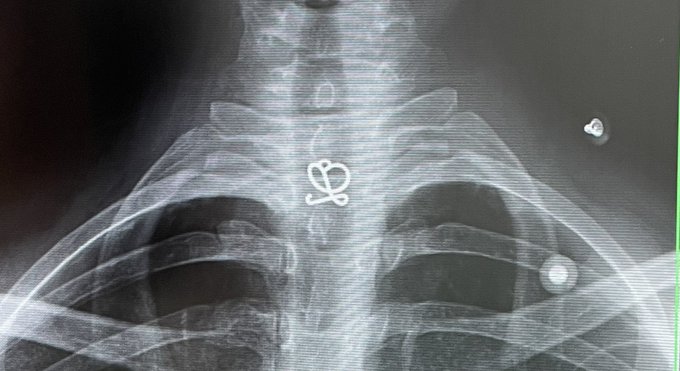

朝から首が痛くて(心配ご無用です❣️)病院行って念のためレントゲン撮ってもらったら、ロエベのカーディガンについてるロゴ透けてた、おしゃれレントゲン pic.twitter.com/v1tH6k1Nrv